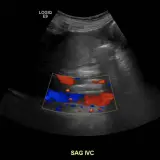

Over 2,100 interactive radiology cases, curated by radiologists for your level of training. Scroll, window, and view cases full screen — just like on PACS. Click linked findings in each writeup to jump straight to them on the image. Cases include sample reports, a focused discussion section, original illustrations, and videos.

Casos totalmente interactivos con las herramientas que esperaría de un PACS: scroll, ventana, zoom, pan, mediciones, ROI y modo de pantalla completa.

• Anotaciones enlazadas

Anotaciones extensas resaltan los hallazgos clave directamente sobre los casos. Haga clic en los hallazgos enlazados dentro de la descripción del caso para saltar a su ubicación exacta en el estudio.